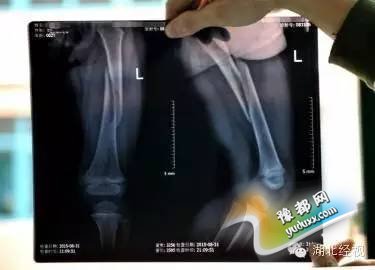

“糟了,断了!”彭女士走过去,把孩子抱起来,这时她的手摸到孩子的左腿,发现里面的骨头已经松动了。彭女士把情况告诉了该游乐设施的老板,双方一起把孩子送到了附近一家医院检查,拍片显示:佳佳的左腿股骨干螺旋形骨折。孩子跳了4小时蹦床,把腿跳断了!